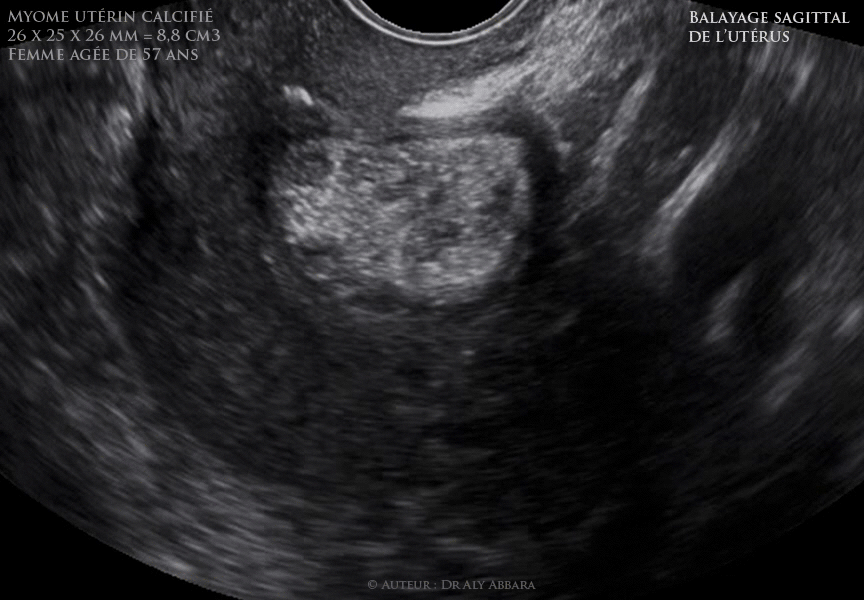

Utérus :  myome intra-mural antérieur calcifié chez une patiente âgée de 57 ans

Utérus : myome intra-mural antérieur calcifié chez une patiente âgée de 57 ans, ménopausée depuis l'âge de 52 ans.

Il s'agit d'un myome asymptomatique, non évolutif depuis 5 ans.

• Séquences vidéo et images échographiques montrant (sur des coupes sagittales, et frontales) un utérus rétroversé portant un myome de structure hyperéchogène, bien limité, mesurant 26 x 25 x 26 mm de diamètre, soit 8,8 cm3 de volume ; intra-mural antérieur, de classe 4 selon le FIGO.